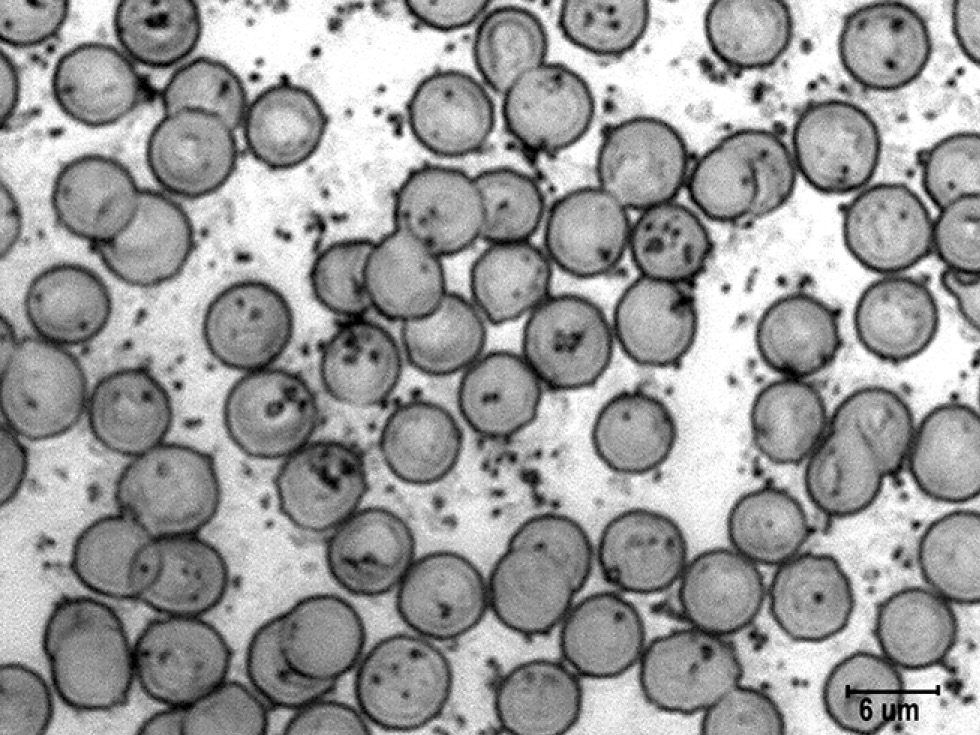

Введение анаприлина сопровождалось снижением числа гранул катехоламинов всех размеров: мелких — в 1,7 раза, средних — в 2,8 раза (p <0,05), крупных — в 2,3 раза (р <0,01). Суммарное число гранул катехоламинов сократилось до 67±8,9 шт., или в 2,3 раза (р <0,01) (табл. 2, рис. 2). Столь резкое снижение числа гранул катехоламинов после введения β-адреноблокатора подтвердило, что гранулы на поверхности эритроцитов связаны именно с β-адренорецепторами их мембран. Следует подчеркнуть, что после введения анаприлина число гранул катехоламинов уменьшилось в основном за счёт гранул среднего и крупного размера, число мелких гранул изменилось в меньшей степени.

Рис. 2. Гранулы катехоламинов на поверхности эритроцитов в мазках крови крыс после введения блокатора β-адренорецепторов. Импрегнация азотнокислым серебром с докраской эозином. Ув. ×4000. / Fig. 2. Granules of catecholamines on the surface of erythrocytes in the blood smears of rats after the administration of a β-adrenergic receptor blocker. Impregnation with silver nitrate and final staining with eosin. Magnification, ×4000.